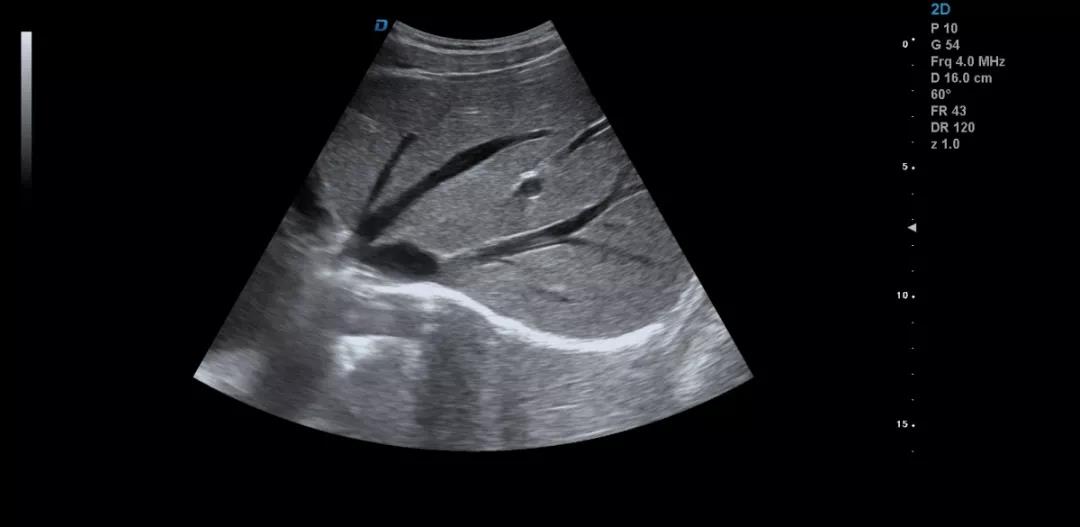

彩超機(jī)是每個醫(yī)院常見的診斷設(shè)備,很多人都不陌生。可能大家認(rèn)為彩超機(jī)檢查醫(yī)生很輕松,其實(shí)不然,彩超檢查醫(yī)生也是需要精湛的操作技術(shù),專業(yè)的判斷才可以的。下面小編和大家一起來看下利用彩超機(jī)檢查肝臟超聲的方法。

彩超檢查不同于其他的影像學(xué)檢查方法,彩超檢查的結(jié)果與操作者的技術(shù)、經(jīng)驗(yàn)、手法、檢查細(xì)致程度等很多因素密切相關(guān)。

眾所周知,肝臟有很多檢查死角,成為超聲檢查的盲區(qū),如肺和骨所掩蓋處,肝右前上段及右后上段的膈頂部,左外葉外側(cè)角區(qū),沿肝臟表面的肋骨下區(qū)等等部位,只有極其細(xì)致的檢查配上精巧的手法才能盡可能的顯示清楚這些部位。

如果我們能夠細(xì)致的檢查每個病人,所謂的肝臟死角能夠盡可能的探測到,肝臟的死角其實(shí)只有膈頂部,其他的部位如果能細(xì)致檢查都可以探測到。

發(fā)現(xiàn)肝臟病變時要多切面多角度掃查,可以了解病變的解剖位置并排除假陽性。